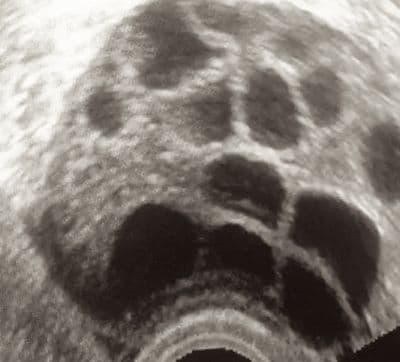

The antral follicle count is a method for ovarian reserve testing using transvaginal ultrasound.

Ovarian follicles are the name given to the small ovarian cysts that contain eggs. At the beginning of a menstrual cycle, using ultrasound you can visualize and even measure these tiny follicles in the ovary. A normal follicle will be less than 9 or 10 mm in diameter.

Studies differ on the exact number of follicles that would be considered decreased but most would be in agreement that a total number of less than four is very low and therefore predictive of decreased ovarian reserve.